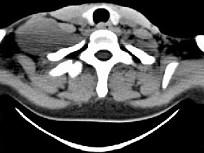

问题 女,47岁,下颈部触及一包块约五年余,CT如图所示,最可能诊断为 ( )

选项 A、副神经节瘤 B、巨淋巴结增生症 C、血管瘤 D、神经鞘瘤 E、滑膜肉瘤

答案 D